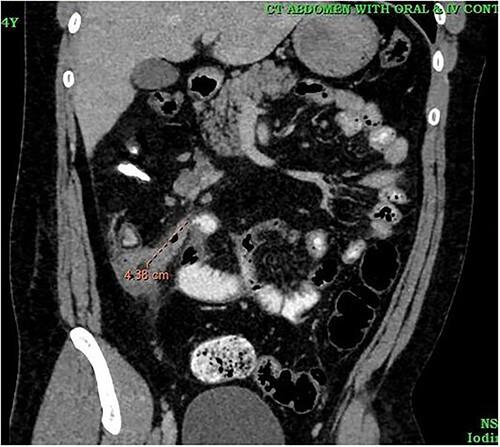

Tuberculosis (TB) remains as a significant global public health issue, especially in developing and underdeveloped nations. Extrapulmonary TB comprises 20% of the TB cases; of which 34.4% were in the lymphatics, 25.2% pleural, followed by 12.8% gastrointestinal and 9.4% in the central nervous system. Ileocecal involvement is the most common among gastrointestinal TB. Although it can cause secondary damage to the appendix, primary type of appendicular TB is rare and can occur with no other signs of the disease. A high index of suspicion is necessary for early diagnosis and treatment of TB. Similarly, stump appendicitis (SA) is a rare and delayed complication of appendectomy. Here we report a case of primary appendicular TB in a patient presented to a multi-specialty hospital in Kerala, India, with SA.

结核病(TB)仍然是一个重大的全球公共卫生问题,尤其是在发展中国家和不发达国家。肺外结核占结核病病例的20%;其中34.4%发生在淋巴管,25.2%在胸膜,其次是12.8%在胃肠道,9.4%在中枢神经系统。回盲部受累是胃肠道结核中最常见的。虽然它可导致阑尾继发性损害,但原发性阑尾结核很少见,且可在无其他疾病体征的情况下发生。对于结核病的早期诊断和治疗,高度的怀疑指数是必要的。同样,残端阑尾炎(SA)是阑尾切除术后一种罕见的延迟并发症。在此,我们报告一例原发性阑尾结核患者的病例,该患者在印度喀拉拉邦的一家多专科医院就诊,患有残端阑尾炎。